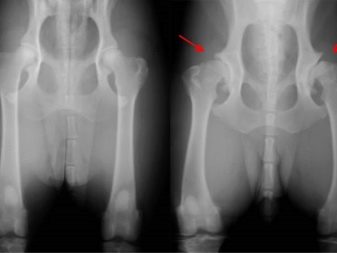

For example, they often have dysplasia of the hip joints, diabetes, and hypothyroidism. Among other common ailments characteristic of dogs of this breed, such problems as aortic stenosis, melanoma and cataract can be noted.

hip dysplasia